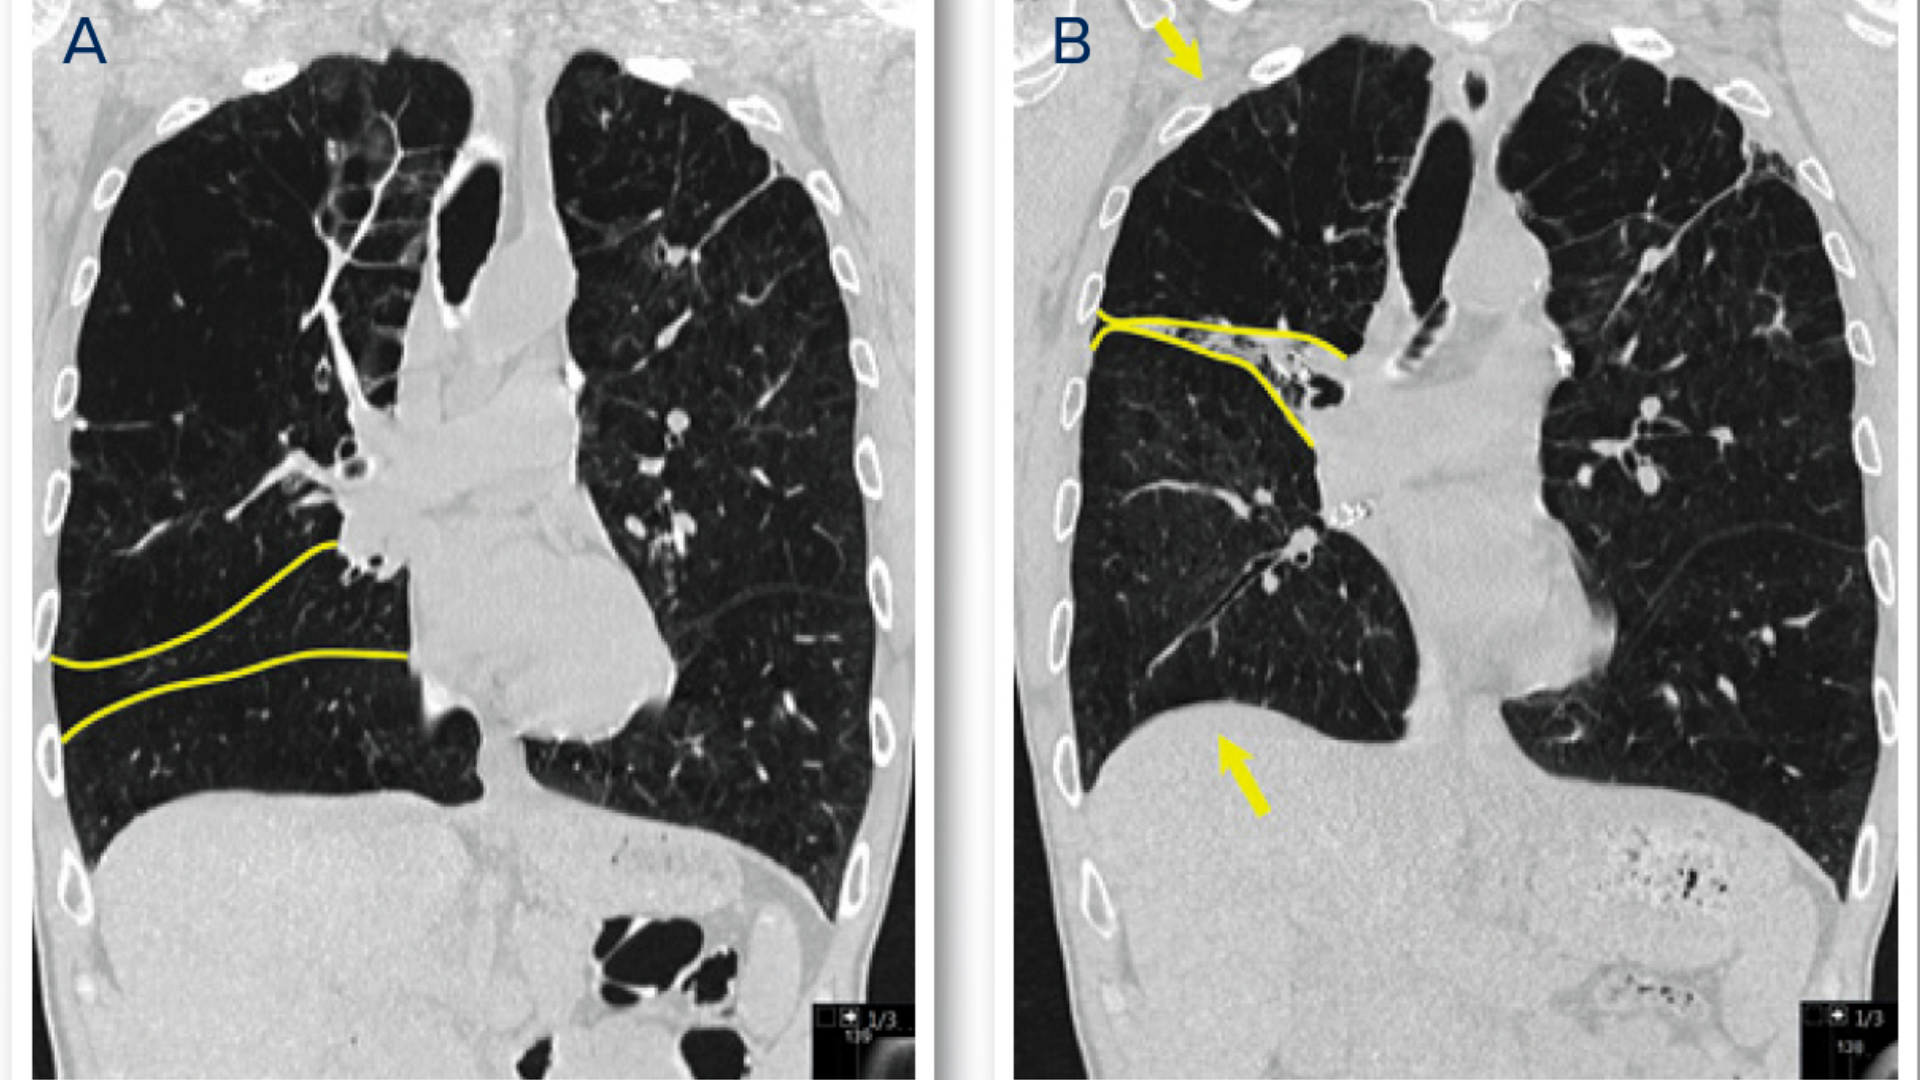

Side-by-side lung scans, labelled A and B, show the difference in lung shape before and after BLVR. Yellow outlines and arrows indicate the movement and decreased size of the lobes and diaphragm.

Figure 1: Coronal view of the right lung prior to therapy (A) and following BLVR (B), where is demonstrated significant reduction of the right upper lobe volume (upper arrow), complete deflation of the right middle lobe, and return of the diaphragm to a more natural configuration (lower arrow).

At bronchoscopy, a direct measure confirmed the absence of collateral ventilation to the right middle lobe and right upper lobe (Figure 1A).

A total of seven endobronchial valves were then deployed in these targeted lobes. CT scans following his procedure demonstrated substantial reduction of right lung volume and return of the diaphragm to a more natural shape (Figure 1B).